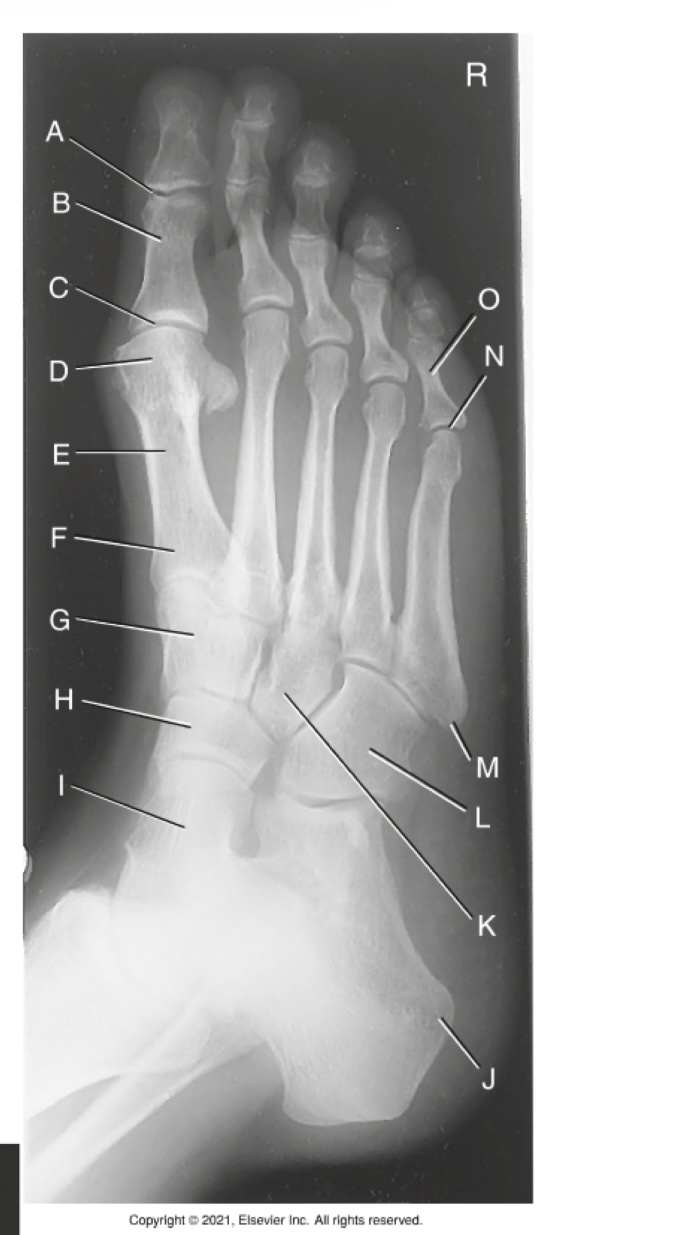

(AP AXIAL FOOT) what is A?

First metatarsophalangealjoint

what is B?

First tarsometatarsal joint

what is C?

Medial cuneiform

what is D?

Navicular

what is E?

phalanges

what is F?

metatarsals

what is G?

tarsals

what is H?

cuboids